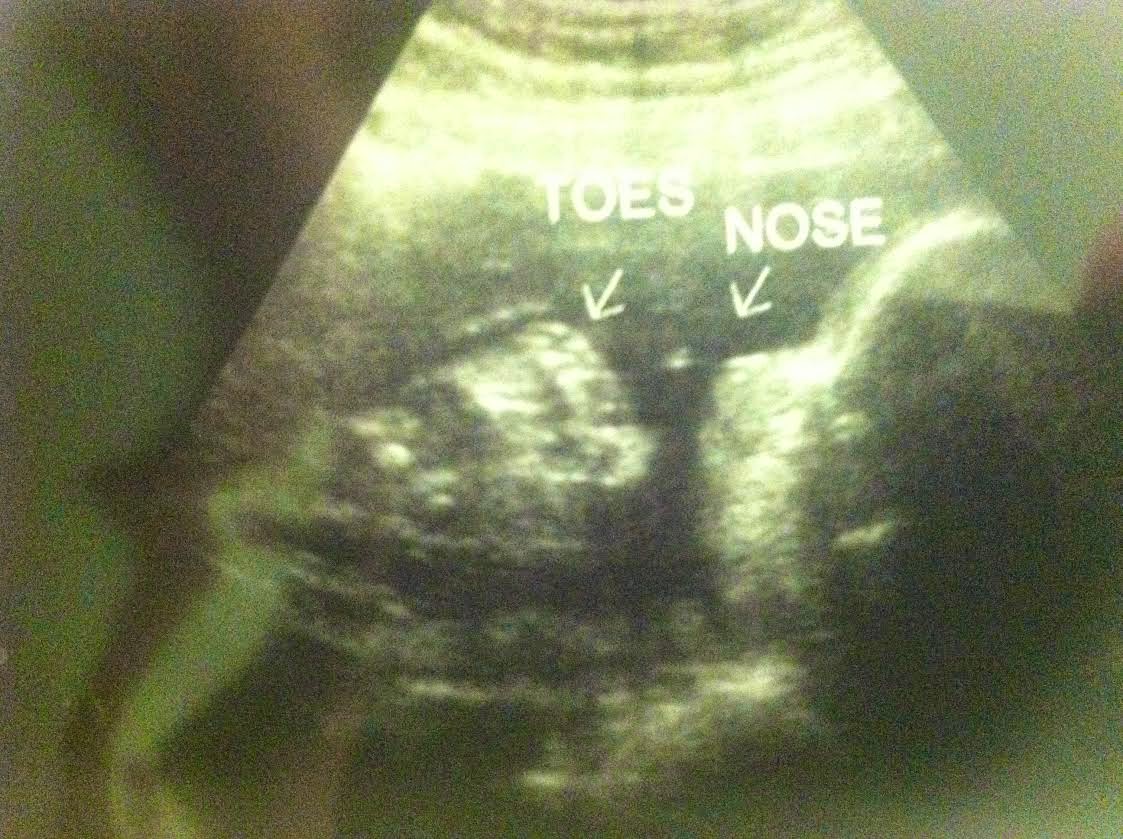

~29 Weeks~

Here is our sweet baby girl at 29 weeks. The toe is going for the mouth. How adorable?